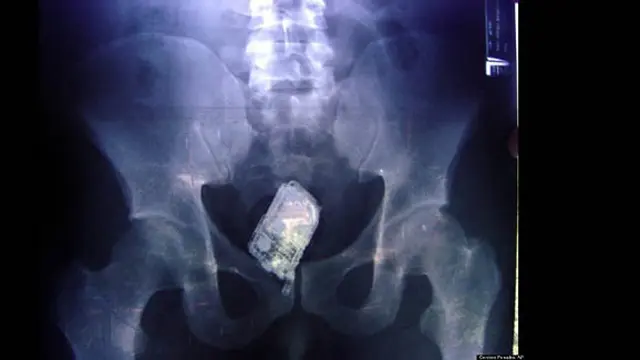

Tahanan Penjara Telan Handphone

Tidak seharusnya ada handphone di dalam perut manusia. Namun lihatlah bagaimana ada sebuah handphone tertinggal di dalam perut hasil foto rontgen di atas. Handphone itu bisa ada di perut atau tepatnya di usus karena... ditelan. Ya, ditelan, Anda tidak salah baca.

Pada bulan September 2006, hasil foto rontgen menunjukkan handphone tertinggal di dalam perut empat tahanan di El Salvador. Sistem penjagaan yang ketat membuat pada tahanan tidak diizinkan membawa handphone. Petugas penjara yang curiga melakukan foto rontgen pada empat tahanan tersebut, dan begitulah hasilnya.